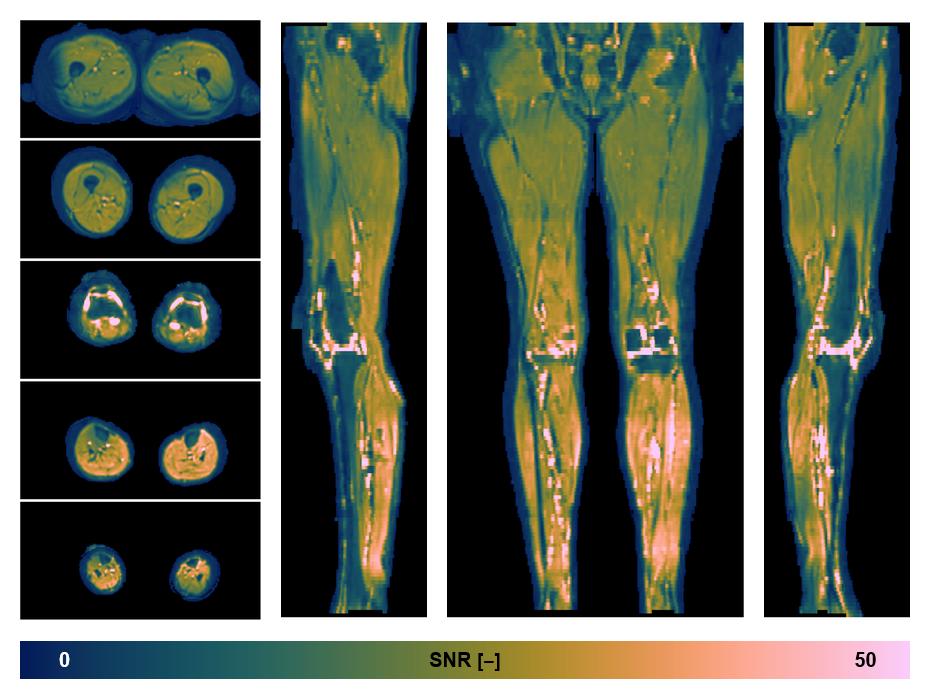

• SNR of the unweighted image

SNR distribution of the unweighted diffusion data.